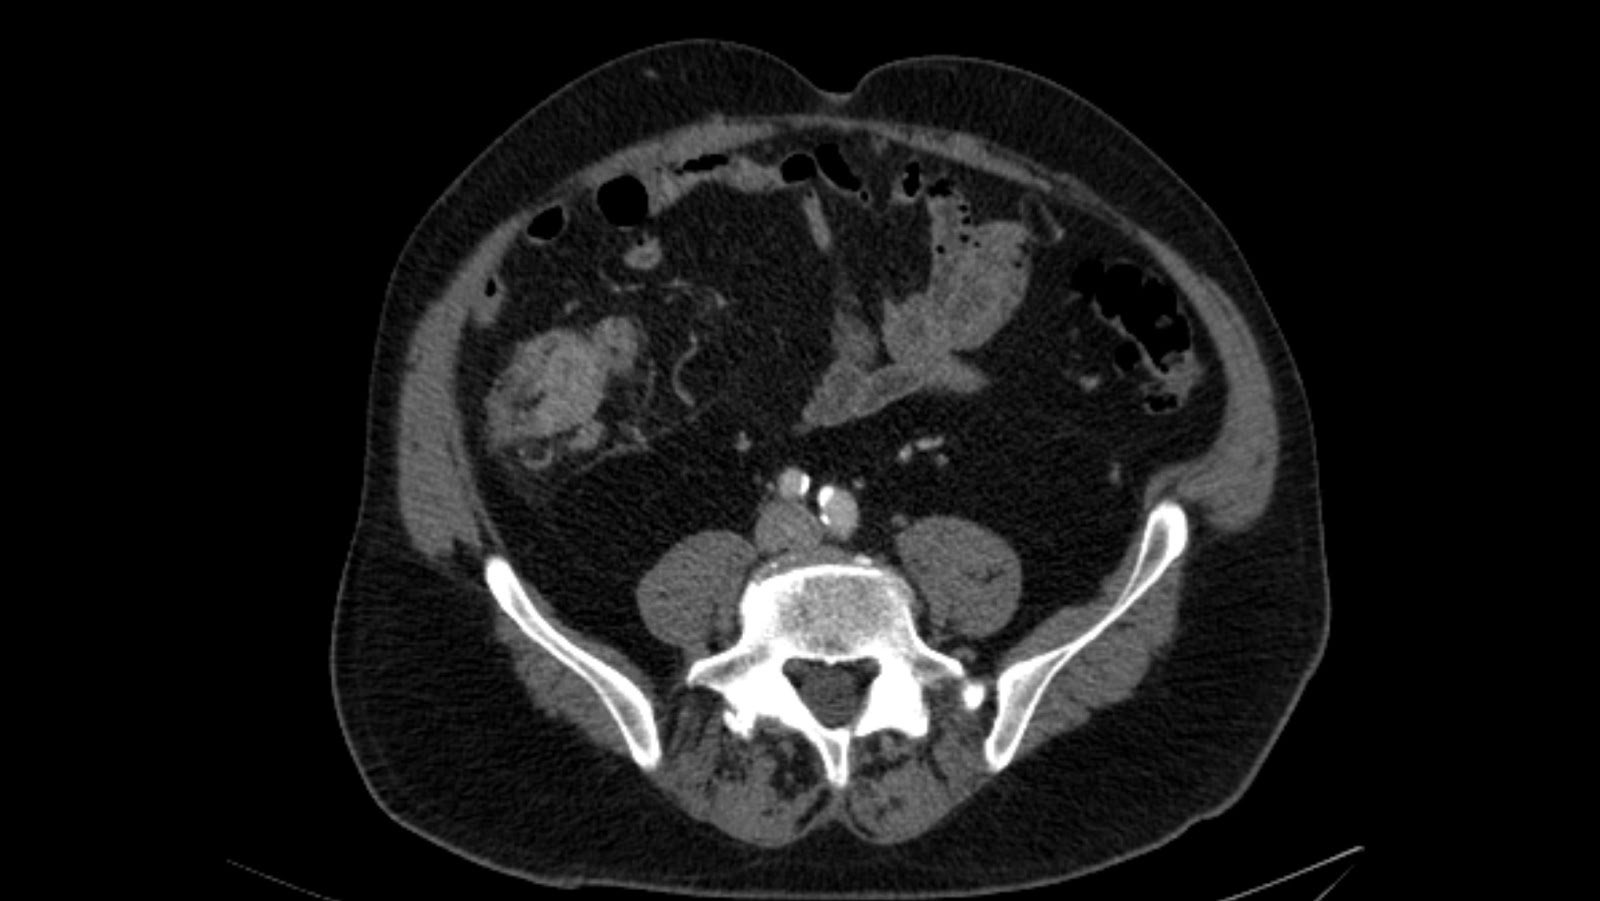

Radiografía de tórax: masa redondeada de gran tamaño que parece proceder de mediastino anterior con imagen en suelta de globos. TAC Abdomen-pelvis: extensa masa localizada en mediastino anterosuperior, heterogénea con múltiples zonas hipodensas en probable relación a necrosis.. El coriocarcinoma se incluye dentro de los no seminomas.

La radiografía de tórax muestra imágenes nodulares múltiples en ambos campos pulmonares («en suelta de globo») , TAC toracoabdominal confirma los nódulos pulmonares bilaterales, adenopatías mediastínicas anteriores, precarinales y retroperitoneales que desplazan vena porta.